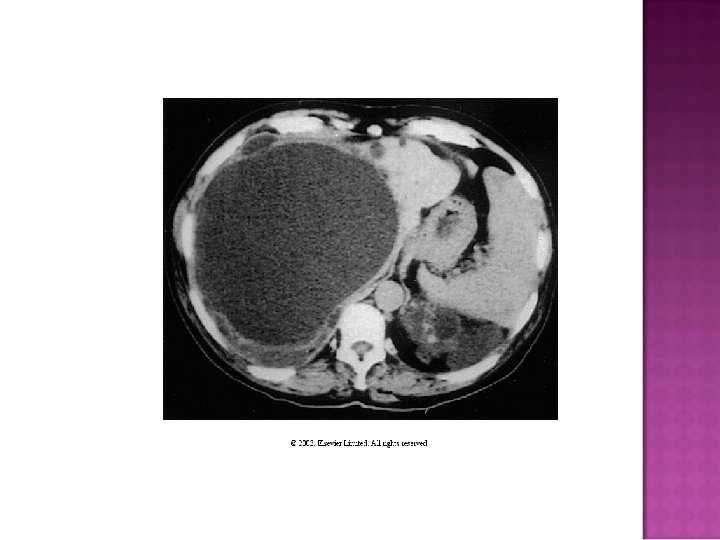

Easy diagnosis in overt disease: flank pain, positive family history, CRI, large kidneys with multiple bilateral cysts on CT or sonogram Cysts in liver, pancreas, and spleen What do you do with otherwise unexplained CRI, hematuria, with negative family history?